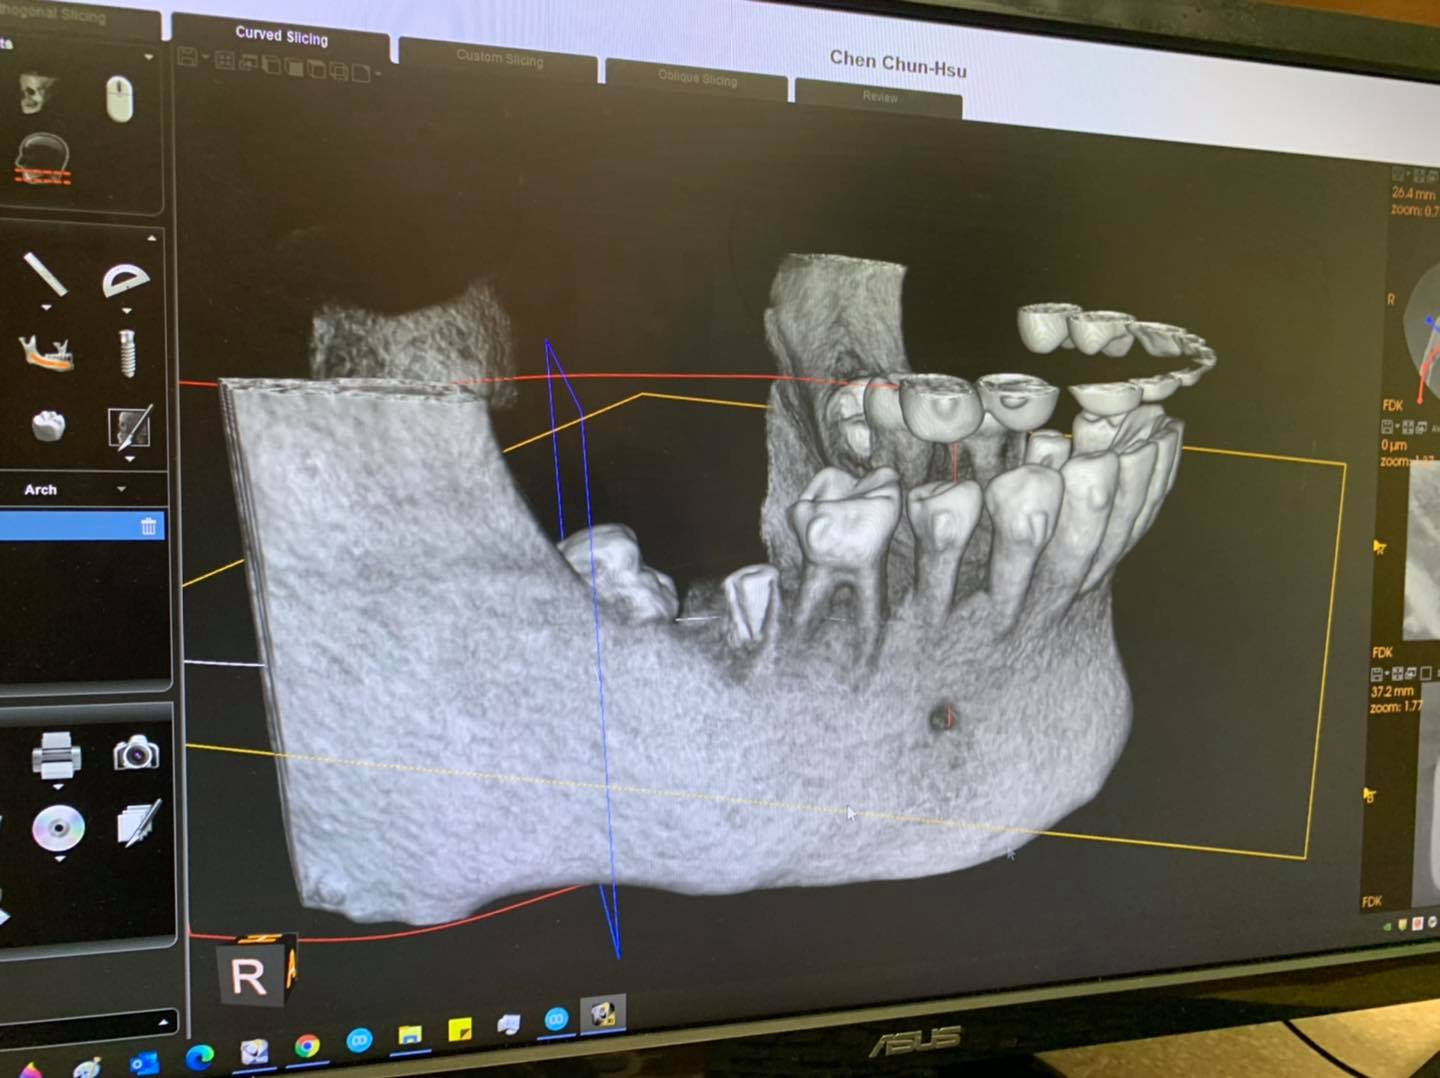

牙醫建議我到醫學中心的口腔外科做全身麻醉,拔拔看。但透過關係,找到一位經驗豐富的台灣牙醫教授要幫我拔,但他需要我回台灣後,拉鋼線,把智齒牽引在前面的植體上,三個月後,等拉出來一些,再拔,這樣比較不會傷到下面的三叉神經(否則傷到就半邊嘴唇永遠麻麻的,無知覺,一輩子喔!)。

但我真的等不下去了,因為這顆爛智齒已經影響到前面的植體和臼齒了!

我實在不想全麻,終於加州的這位台裔牙醫看過我的X光片後,說不用全麻,而且大概花十分鐘可以拔起來。

因為疫情,員工先到停車場迎接我,用雙氧水漱口。先填防疫表格。進診所拍2D和3D的X片,看片,解說,打麻藥,填問卷,同意書簽名,填完表格大概就花了20分鐘,麻藥已充分發揮作用了,牙醫就來,用鐵器撐住另一邊的嘴,叫我咬住。然後她跟我說先清傷口。因為我智齒已發炎,上面牙肉已是紫色,還有一個破洞。